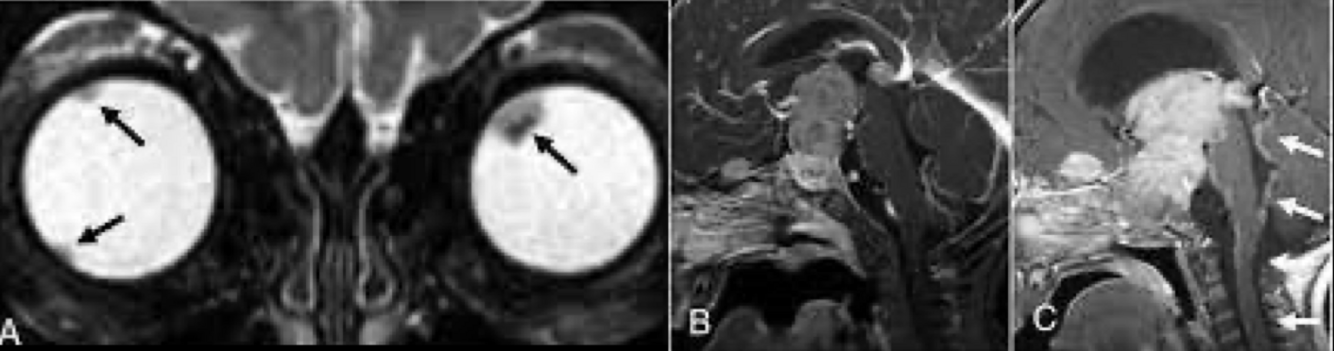

T1: Agrandamiento de músculos

extraoculares.

T2: Aumento de señal en músculos extraoculares en fases agudas.

Orbitopatia tiroidea en RM